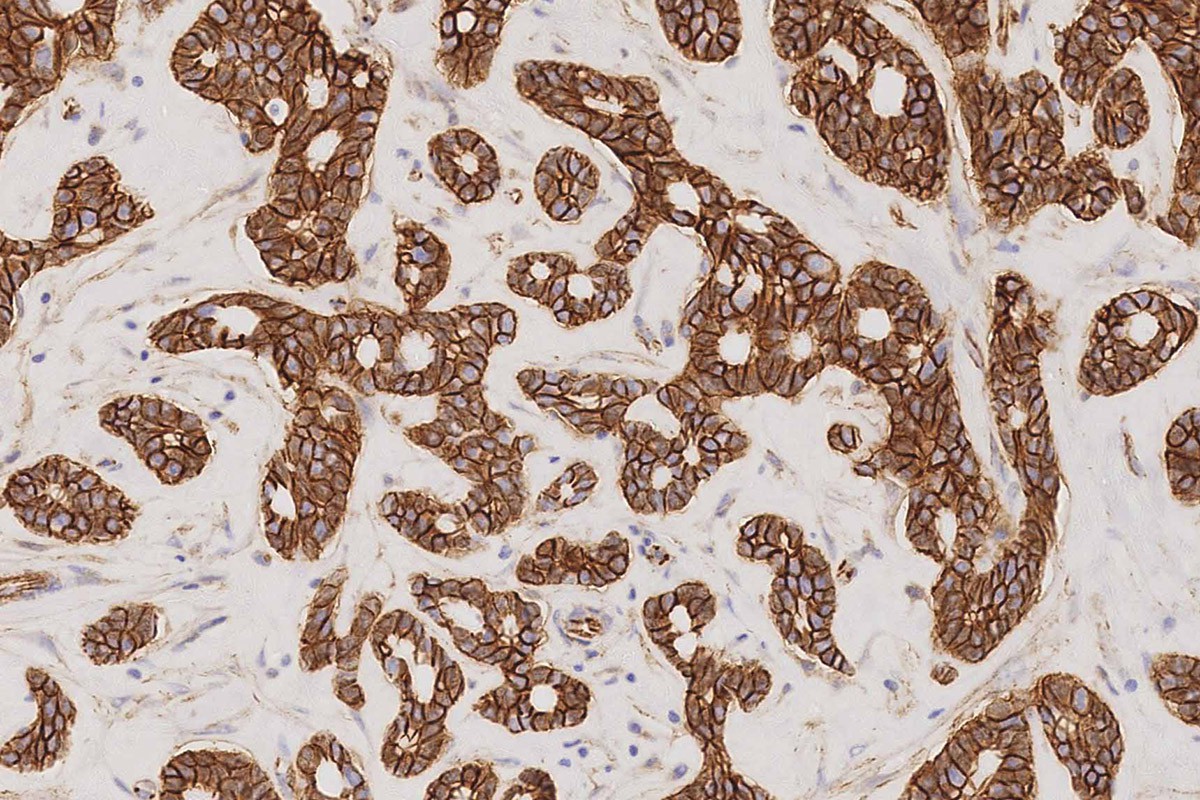

Human breast carcinoma: immunohistochemical staining for p120 Catenin antigen. Note membrane and cytoplasmic staining of malignant cells. p120 Catenin: clone EP66

p120 Catenin is a regulator of cell-cell adhesion, achieved through interaction with classical and Type II cadherins. Evidence also exists for a role in the regulation of cadherin availability on the cell surface. p120 Catenin also regulates actin dynamics, placing it as a potential master regulator of the cell motility/cell adhesion phenotypes.

Recent studies have suggested a tumor-suppression role for p120, with loss of p120 expression implicated in the development of a tumor microenvironment and induction of metastatic progression. The expression of p120 Catenin has been highlighted in early lobular breast neoplasias.